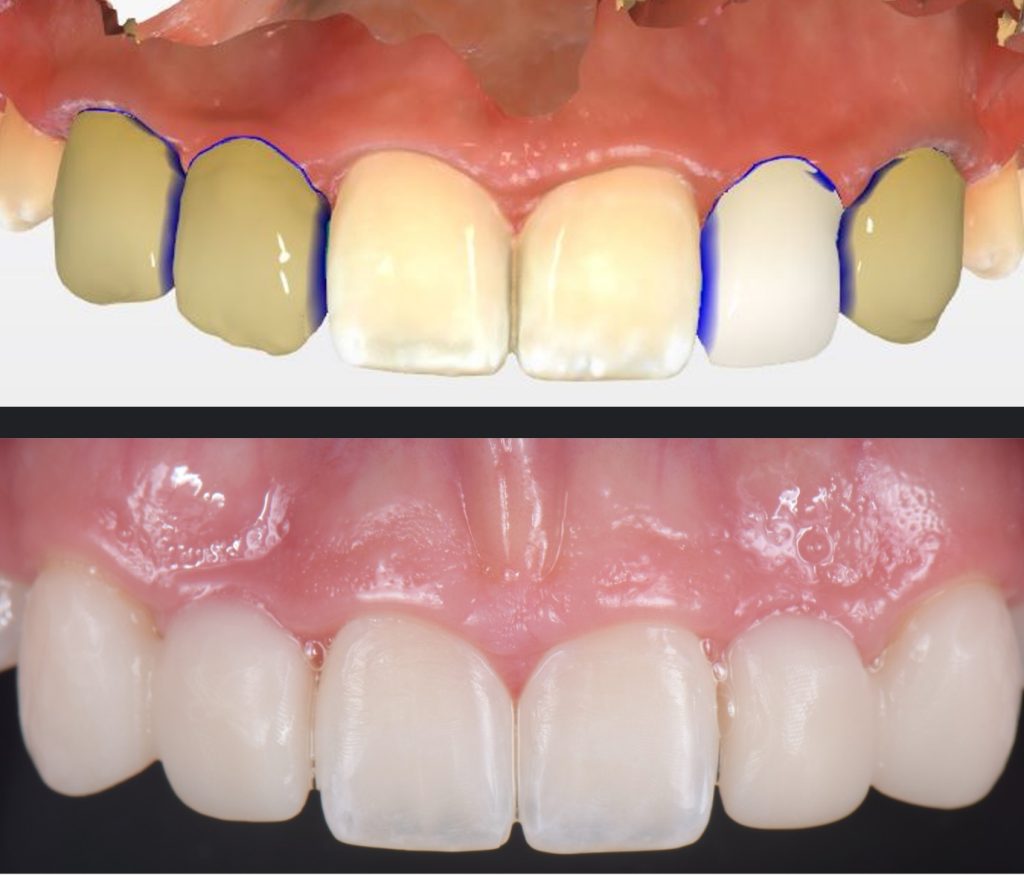

In this case, a 16-year-old female (Figs. 13-23) presented with congenitally missing lateral incisors with significantly undersized canines that were out of occlusion. Both these specific features meant that from a functional and esthetic standpoint (tooth position and size), the canines required additional contour to attain a favorable occlusal contact and a more dominant contour, characteristic of a maxillary canine.

So, I needed to make sure that there was enough space for the restorative material. A purely additive wax-up was required to attain a mockup, verifying that the proposed contours were esthetically pleasing. This can be obtained either by an analogic approach (Fig. 15) or a digital approach (Fig. 16).

Incisally, there was no reduction required, the reduction was minimal, and from a cervical perspective, a 0.5 mm finish line was prepared (Fig. 17). This allowed our team to do a fundamentally additive design.

The undersized canines were out of function, removing all protective coverage for the lateral incisors. This provided a unique opportunity and indication for the most conservative scenario of a cantilevered RBFDP.

When considering a zirconia crown, we needed to ensure there was sufficient room for the wall thickness to be a minimum of 0.3 mm (ideally between 1.0 mm and 1.5 mm), an incisal reduction of 2.0 mm, and a visible and continuous circumferential chamfer with a reduction of at least 0.5 mm at the gingival margin. The patient’s preliminary condition allowed us to accomplish these space requirements with hardly any tooth reduction (Fig. 17).